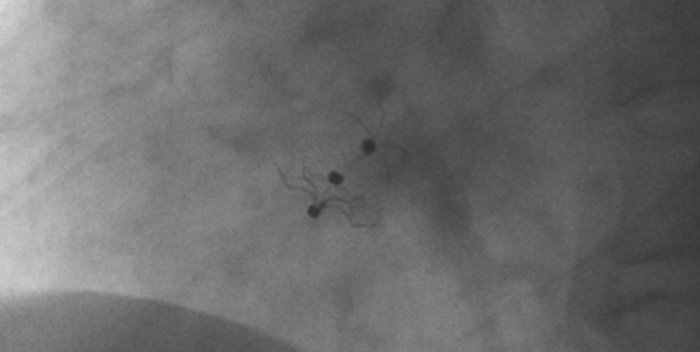

造影顯示PFO封堵完全,無殘余分流, 試驗器械充分舒展并貼合良好

影像顯示試驗器械適應性貼合于房間隔兩側且穩定